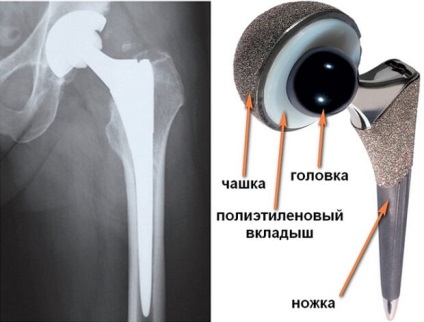

Este un total (complet) și o revizuire (repetare).

În cazul în care înlocuirea totală înlocui complet toate componentele îmbinării.

Dar, uneori, pacienții trebuie să facă revizia de inlocuire a soldului. Mulți oameni trăiesc cu endoproteze pentru o lungă perioadă de timp, fără nici o senzație de disconfort.